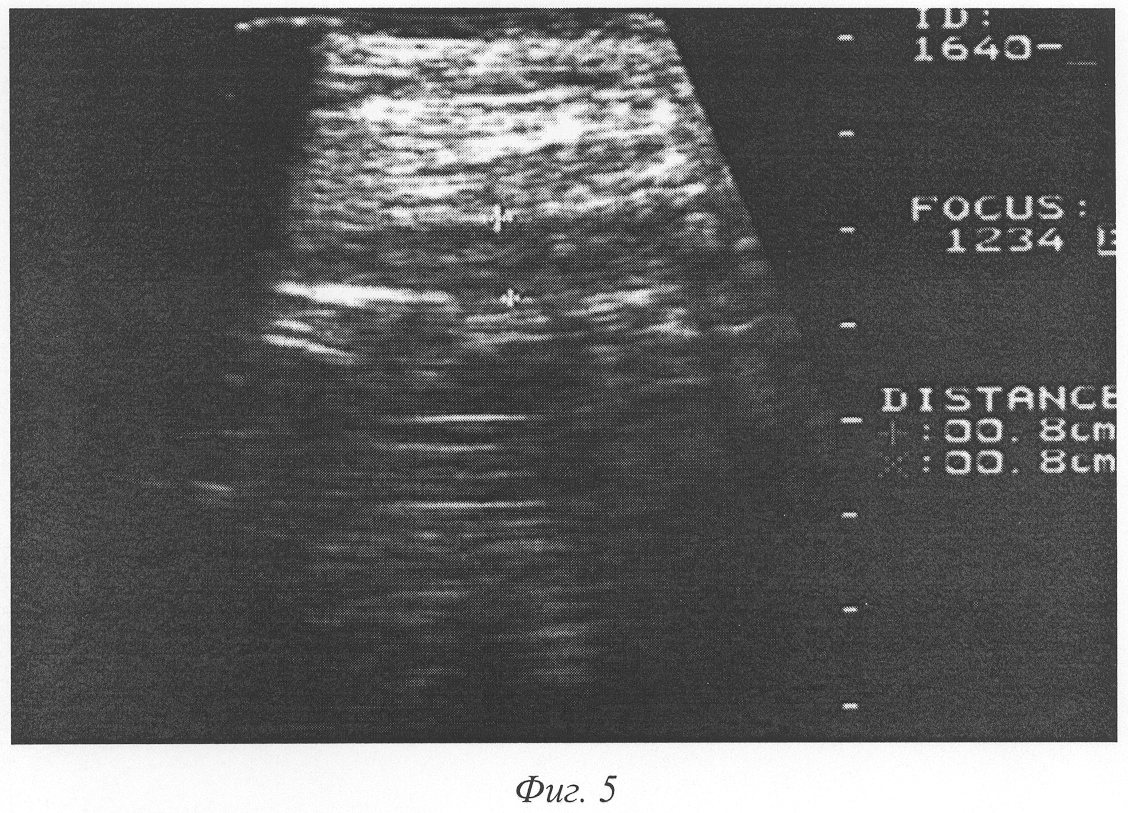

Фиг.5 – эхограмма передней брюшной стенки живота на 5-й день после аппендэктомии больного К., 16 лет. Определяется гипоэхогенная зона (обозначена крестами) на глубине апоневроза наружной косой мышцы живота толщиной 8 мм.

Пример 3. Больной К., 16 лет, история болезни №1625, поступил в клинику 12.03.2001 года с диагнозом «Острый аппендицит». Диагноз подтвержден данными анамнеза, объективного обследования и лабораторными показателями. Операция – аппендэктомия. Послеоперационный диагноз: катаральный аппендицит. Операционная рана ушита наглухо. Средняя температура тела в первые 4 суток послеоперационного периода 37,3°С. При сканировании области послеоперационной раны на глубине апоневроза на 3-и сутки гипоэхогенная зона толщиной 6 мм. На 5-е сутки послеоперационного периода толщина гипоэхогенной зоны составила 8 мм (фиг.5). При пальпации области послеоперационной раны отмечается болезненность, инфильтрат четко не пальпируется. Учитывая данные ультразвукового исследования, решено произвести ревизию раны, во время которой вскрыт подапоневротический абсцесс. Рана промыта 3% раствором перекиси водорода, повязка с мазью «Левомеколь». Заживление раны вторичным натяжением.

Данное наблюдение (пример 3) показывает диагностическую и прогностическую ценность предлагаемого способа контроля эффективности лечения послеоперационных ран. На 3-и сутки выявлена гипоэхогенная зона в области мышечно-апоневротического слоя послеоперационной раны толщиной более 5-и мм, которая к 5-м суткам увеличилась до 8 мм, что сопутствовало развитию гнойного осложнения. В данном случае при отсутствии явных клинических признаков воспаления (гиперемия, отек) проведена своевременная ревизия раны, при которой вскрыт подапоневротический абсцесс. Раннее опорожнение гнойника предупредило прогрессирование воспалительного процесса и сократило сроки заживления.